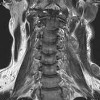

КТ мягких тканей шеи